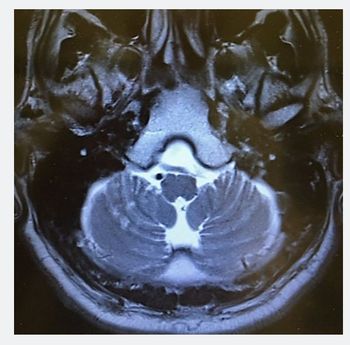

Myosis is accompanied by acute onset dizziness, double vision, and asthenia. What's in your differential diagnosis?

Patient describes 2 short "spells," one of blurry vision and another of tingling in an extremity. Tinnitus begins in your office.